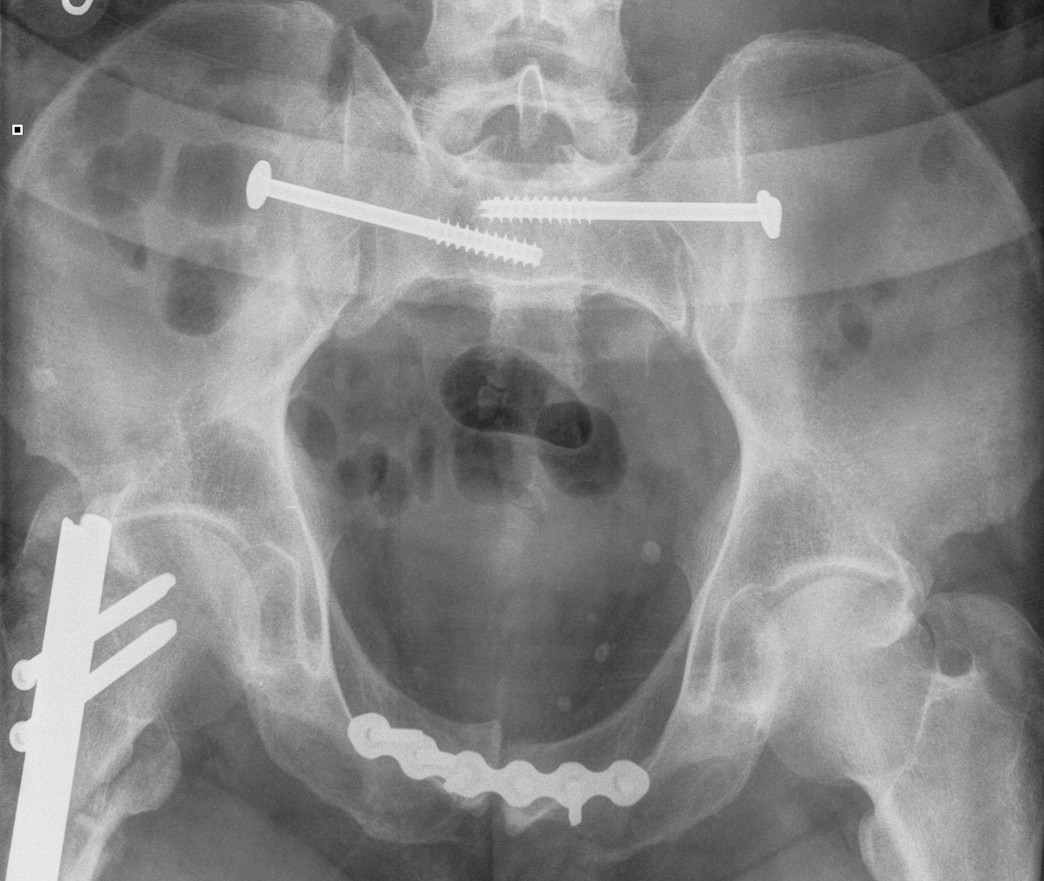

Pfannenstiel approach / Plating Pubic Symphysis

Technique

Set up

- supine on radiolucent table

- foley catheter to decompress bladder

Incision 2 cm above pubis

- through fat and fascia

- split linea alba between rectus

- identify and protect bladder

Incision 2 cm above pubis Identify linea alba and develop plane between rectus

Identify and protect bladder posteriorly

Reduction techniques

- during the reduction care must be taken to avoid trapping bladder or urethra in the symphysis when closing the clamp

- assistant may apply pressure over each iliac crest or an external fixator can be applied

- large pointed reduction clamp can be placed onto each pubic tubercle or through holes drilled in the bone

- expose the medial obturator foramen and application of pelvic reduction forceps thru the medial aspect of the foramen

Superiorly applied plate

- pelvic reconstruction plate

Post-operative XRs: AP, outlet and inlet views